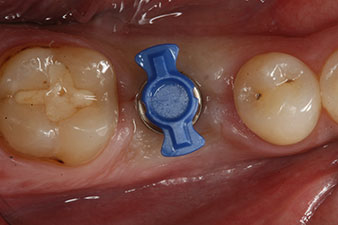

Имплантът е поставен както е планирано след цялостно отстраняване на гранулационната тъкан (blueSky, bredent).

Въртящият момент, използван за машинно-задвижвано поставяне, е 43 Ncm. Освен това, след завинтване на измервателния щифт (SmartPeg), специално пригоден за импланта, стойността на ISQ се измерва със сондата на W&H Osstell ISQ модула.

Този модул е допълнителна екстра към Implantmed на W&H и е закачен към имплантологичния мотор (виж фиг. 11). Липсата на ISQ стойност непосредствено след поставянето е 64 оровестибуларно и 68 мезиодистално (максимална стойност = 100).